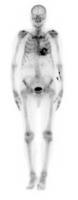

Scintigraphie cardiaque avec traceur osseux

La tomographie permet de confirmer la fixation myocardique du traceur et d’identifier une fixation faible du traceur osseux.

Conclusion :

Hyperfixation intense du traceur osseux dans le cœur grade 3 de Perugini très évocatrice d’amylose TTR en l’absence de chaines légères d’immunoglobuline.

Figure 14 : balayage corps entier

Figure 15 : acquisition tomographique